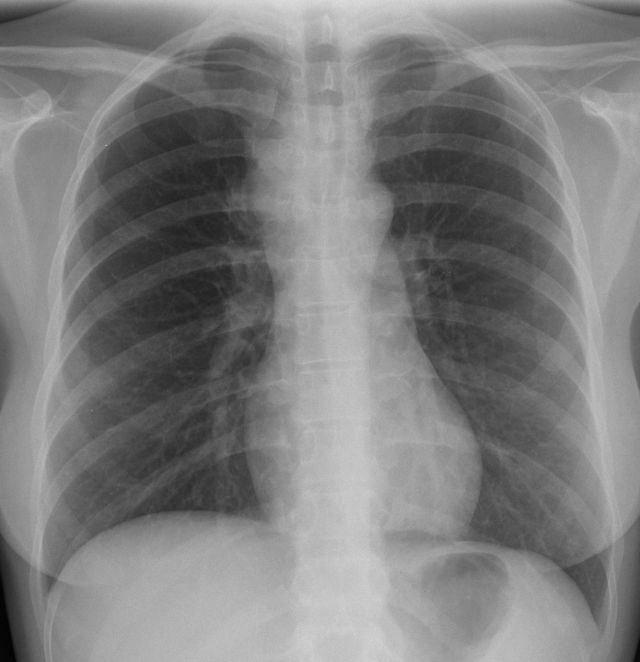

| Mediastinum | 30-jährige Frau therapieresistentem Husten. Das Röntgenbild zeigt eine Verbreiterung des oberen Mediastinums. Bronchoskopisch Impression der Trachea. Mediastinoskopische Biopsie: EBV-negatives klassisches Hodgkin-Lymphom. | ||